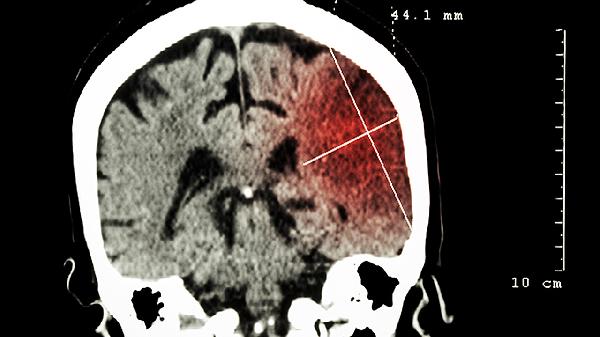

三叉神经痛药物控制无效时可考虑微血管减压术,颅内占位病变需根据性质选择肿瘤切除术或减压手术。术后需定期复查头部CT,监测有无并发症发生。